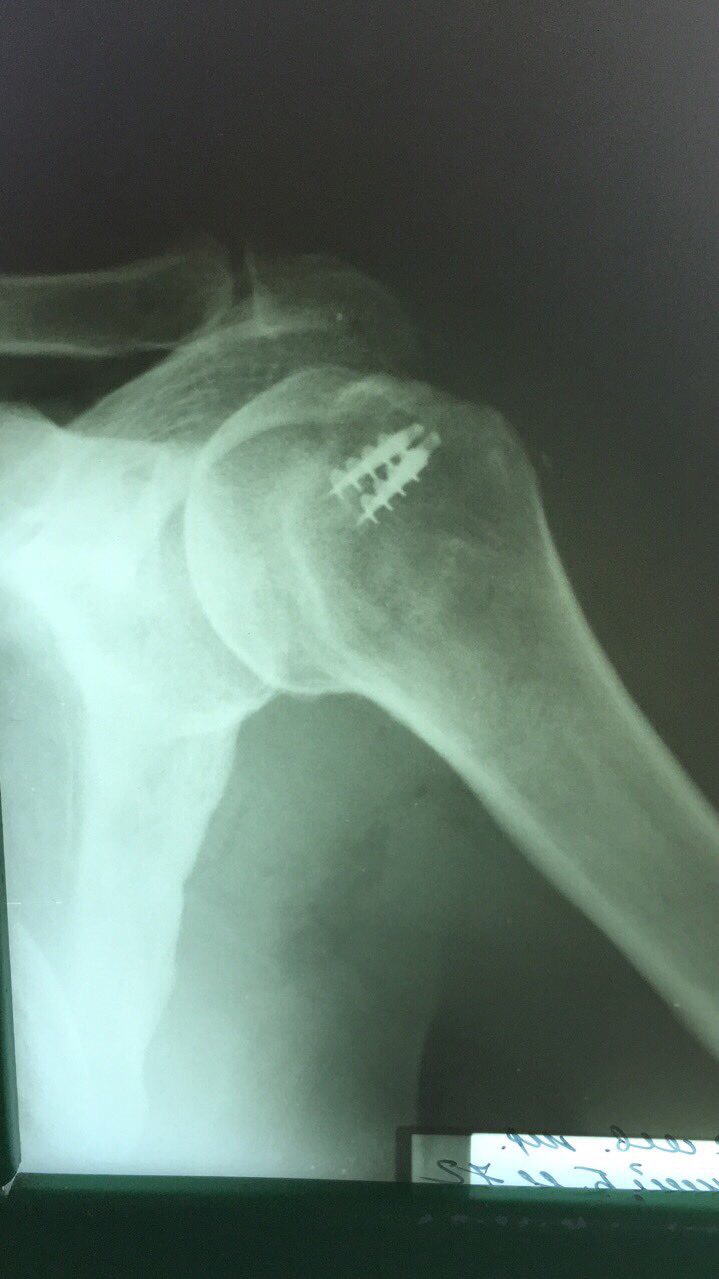

Восстановление сухожилий ротатороной манжеты плеча